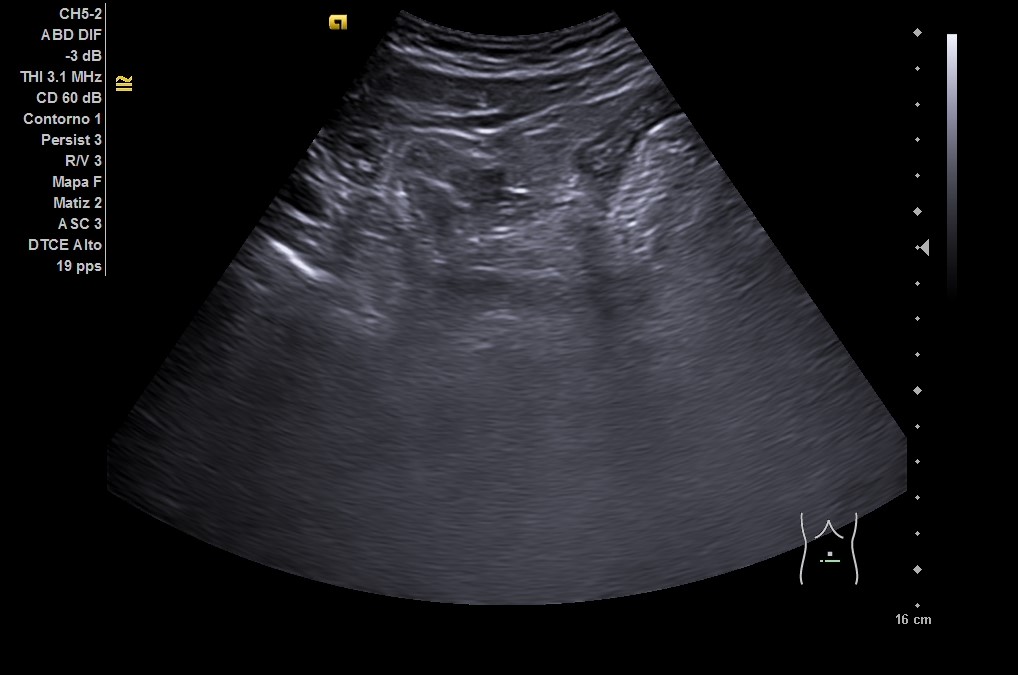

• En urgencias, de inicio se realiza radiografía abdominal sin datos de obstrucción intestinal. Ante persistencia de dolor intenso, leucocitosis y aumento de PCR en analítica, se repite la ecografía (utilizando también sonda lineal) con hallazgo de diverticulitis aguda sigmoidea con datos de peritonitis regional pélvica, y posteriormente se realiza un TC abdominal con conclusión de diverticulitis aguda con pequeños abscesos murales, perforación de un divertículo y peritonitis pélvica.